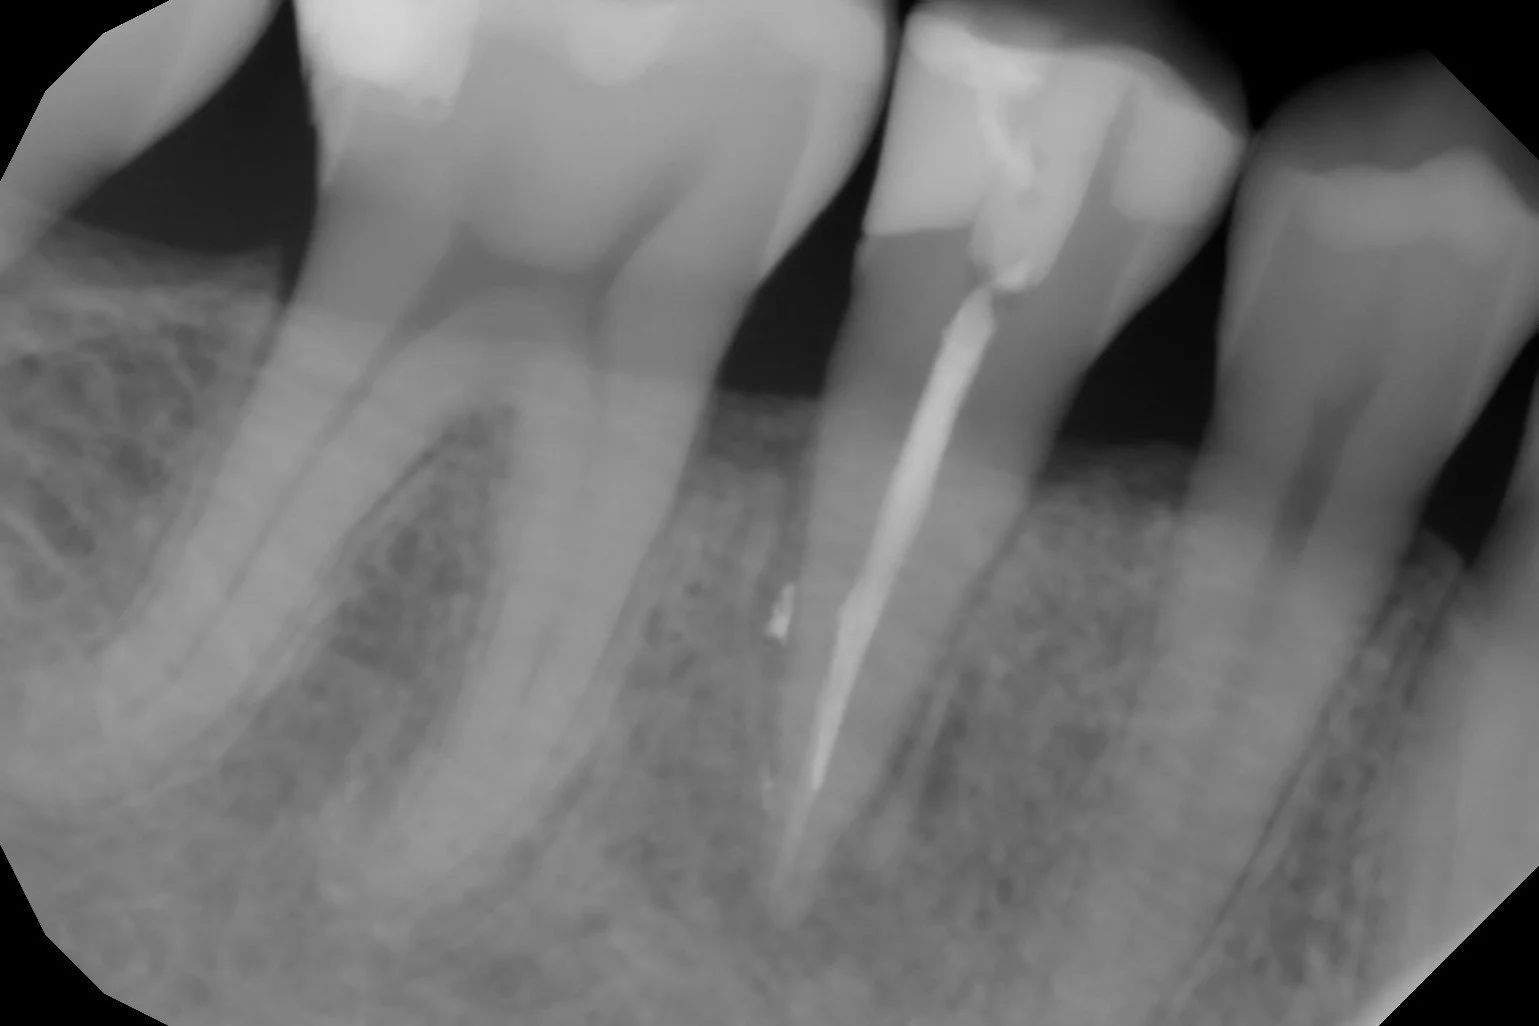

La Endodoncia consigue eliminar el nervio de los dientes con dolor por caries o algún traumatismo y rellenarlo con material biocompatible, conservando el diente sin tener que extraerlo.

En nuestra clínica se realizan endodoncias por un Especialista En Endodoncia tratando desde casos sencillos a casos complejos de retratamientos o fracasos en endodoncias antiguas.

Utilizamos técnicas avanzadas de diagnóstico en endodoncia como la Radiovisiografía Digital, el Localizador de Ápice y Técnicas Rotatorias de instrumentación de los conductos radiculares, utilizando el microscopio en los pacientes que lo requieren.